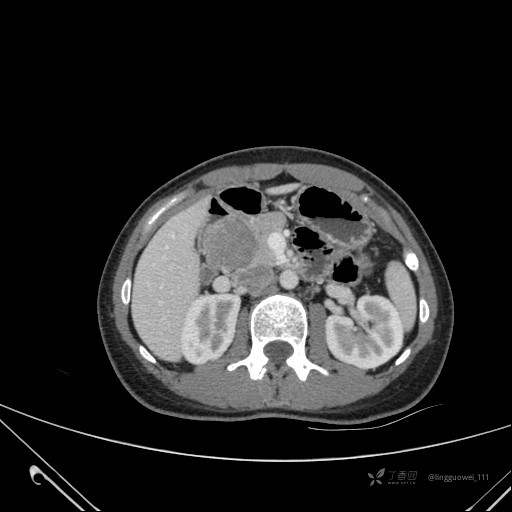

患者性别:女

患者年龄:28岁

主诉:体检发现胰腺病变,行 CT检查。

平扫: